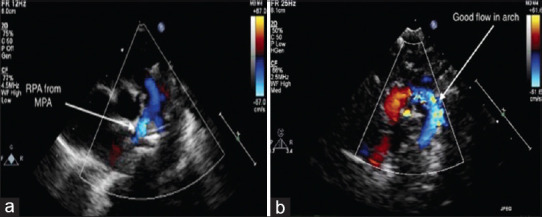

Berry et al. (1982) described a rare syndrome associated with distal aortopulmonary window, aortic origin of the right pulmonary artery, intact ventricular septum, and interruption or coarctation of the aorta. Here, we present the first neonatal case of single-stage repair of Berry syndrome in India. Timely surgery and skilled postoperative care define the short-term and long-term outcomes. Single-staged repair is preferred wherever feasible.